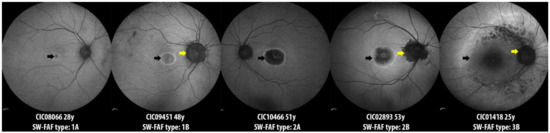

| SW-FAF Phenotype type | n = 35 |

| Group 1 | 6 |

| Group 2 | 21 |

| Group 3 | 8 |

| Peripapillary sparing, No./Total No. (%) | 10/35 (28.57) |

| Estimation of central hyperAF ring enlargement | n = 19 |

| Horizontal diameter, µm/y | 42.88 ± 48.98 |

| Slope | 43.16 ± 47.81 |

| Intercept | 228.60 ± 1689.24 |

| Vertical diameter, µm/y | 39.44 ± 40.90 |

| Slope | 39.36 ± 40.57 |

| Intercept | −24.16 ± 1658.86 |